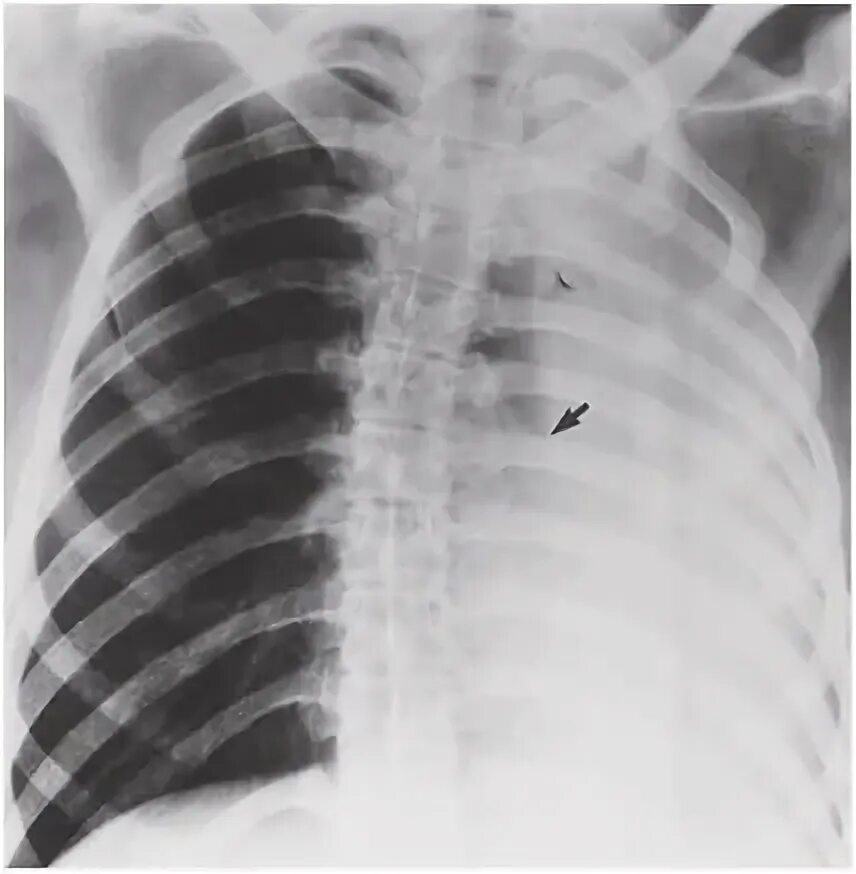

Метатуберкулезные изменения в легких что это означает